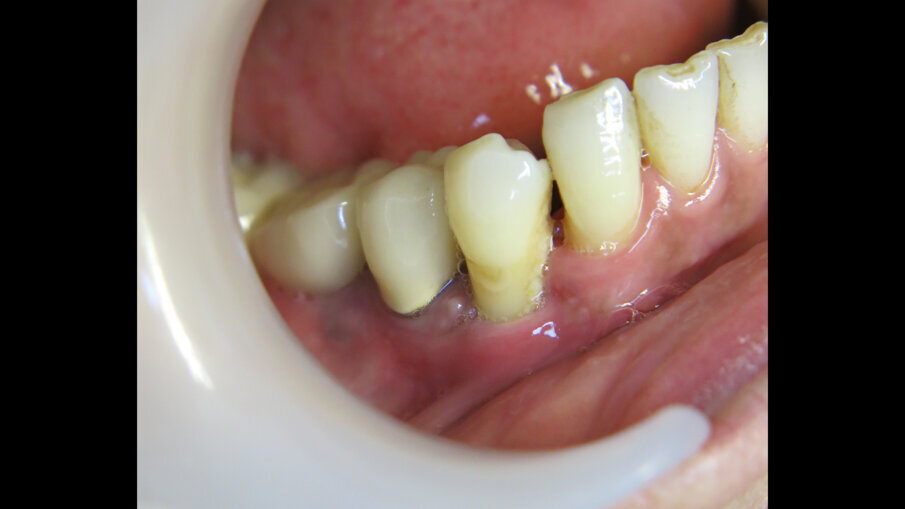

Míra selhání dentálních implantátů je uváděna jako vyšší u kuřáků než u nekuřáků. Cílem studie popsané v tomto článku bylo porovnat míru úspěšnosti 721 dentálních implantátů zavedených u 181 kuřáků s údaji uváděnými v literatuře. V naší studii byly z důvodu vyloučení individuálních faktorů použity implantáty jednoho výrobce a všechny byly zavedeny jedním chirurgem. Kvůli zvýšení míry úspěšnosti u dentálních implantátů zaváděných u kuřáků byl v naší zubní ordinaci zaveden speciální protokol. V následujícím textu jsou podrobně popsány výsledky u dvou pacientů.

Ze 721 implantátů selhalo celkem 65 implantátů. Míra úspěšnosti tedy ve výsledku byla 90,98 %, tedy nižší než v naší předchozí studii provedené u nekuřáků, u nichž byla míra úspěšnosti 98,70 %.2 U skupiny neúspěšných implantátů selhala většina z nich (74,5 %) dva až čtyři týdny po zavedení v důsledku nedostatečné oseointegrace. Periimplantitida se vyskytovala u 20 % neúspěšných implantátů. To lze přičíst špatné ústní hygieně a tvorbě plaku. U 4,6 % případů se periimplantitida objevila v rozmezí jednoho až tří let po zavedení implantátu v důsledku mechanických problémů po úbytku kosti. Nebyla zjištěna žádná souvislost mezi délkou a průměrem implantátu a mírou selhání, ani mezi počtem vykouřených cigaret a mírou selhání implantátu.

Jak již bylo zjištěno dříve, míra selhání dentálních implantátů je u kuřáků vyšší než u nekuřáků, což je způsobeno nedostatečnou časnou oseointegrací a výskytem periimplantitidy. Periimplantitida se objevila u 62 případů zahrnutých do naší studie. Neúspěšná oseointegrace byla hlavním důvodem selhání implantátů. Závěrem je však nutno uvést, že dosažené výsledky byly celkově vynikající.